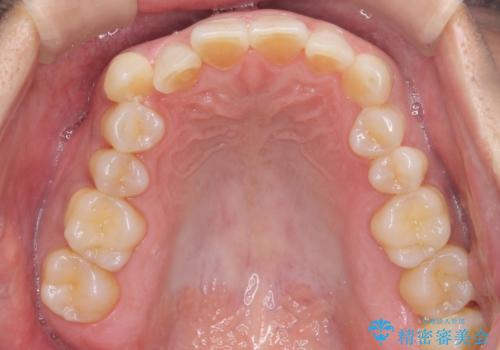

八重歯と下の歯のがたつき マウスピースで

- 右上の犬歯が目立つのが気になる、下の歯並びも治したいとのことで来院。

歯を抜かずに少し削って小さくして並べました。

並びも良くなり、患者様にも喜んでいただきました。

右上の犬歯の歯肉退縮自体は進行する可能性をお伝えしておりましたが、特に変化なく治療できました。